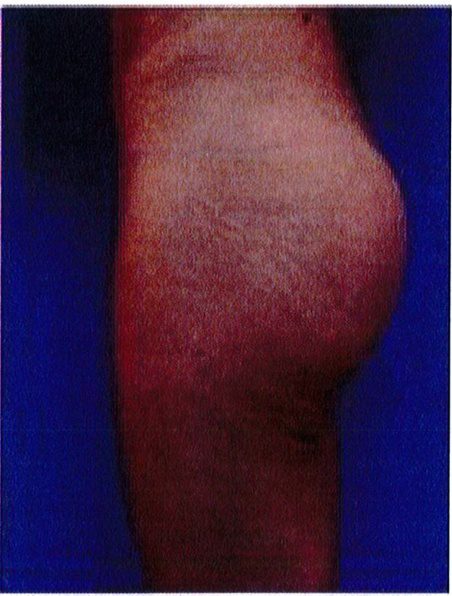

Cuối cùng, một bệnh nhân 48 tuổi có vùng thắt lưng tương đối phẳng. Với tiền sử đã từng hút mỡ và hiện tại đang mong muốn được làm đầy mông để cải thiện hình thể phần thắt lưng (một cách tương đối). Hai khối implant mi- crotextured thể tích 300 mL được đặt ở dưới cân. Bệnh nhân được tiếp tục điều trị bằng liệu pháp siêu âm (dùng sóng siêu âm) sau phẫu thuật nhằm giảm phản ứng viêm tại chỗ. Sau phẫu thuật không ghi nhận biến chứng (Hình 21).

Hình. 21. (A) Hình anh trước và (B) và sau phẫu thuật làm đầy mông của bệnh nhân có vùng thắt lưng tương đối phẳng. Bệnh nhân được đặt khối im- plant dưới cân thế tích 330 mL ở hai bên.